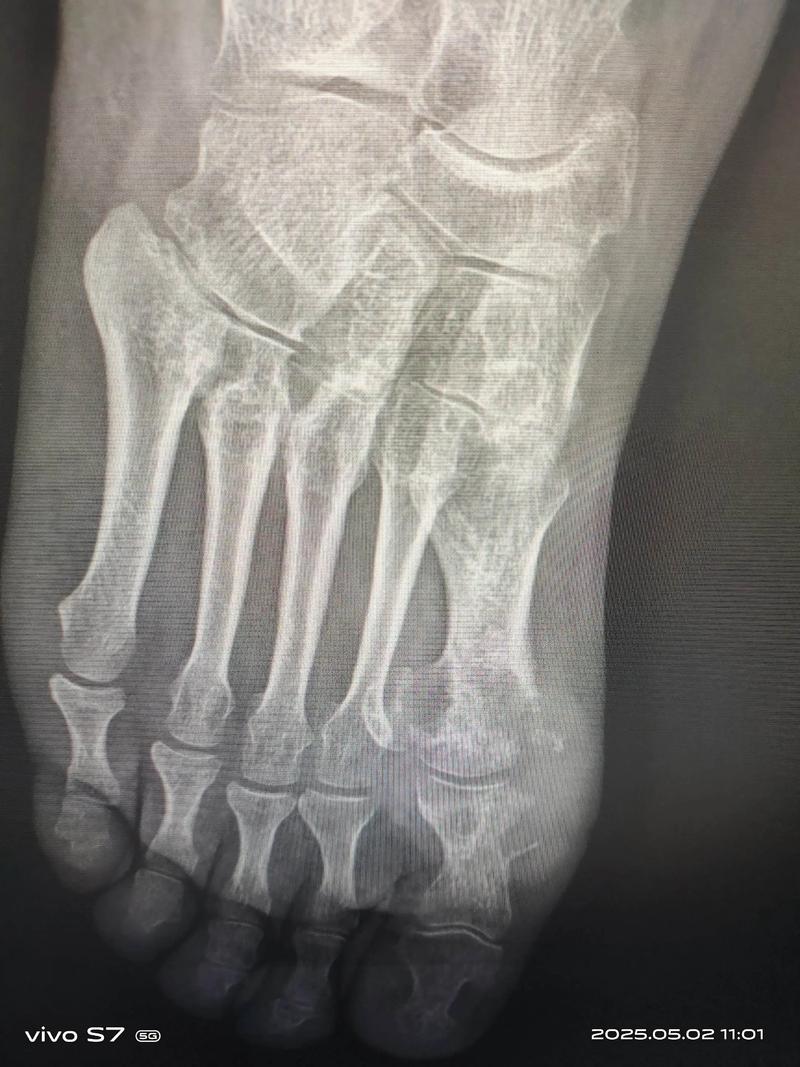

痛风是一种常见的代谢性疾病,主要症状为关节疼痛、红肿、热痛等,右脚大拇指痛风是最常见的痛风症状之一,下面,我将详细介绍右脚大拇指痛风的治疗方法。